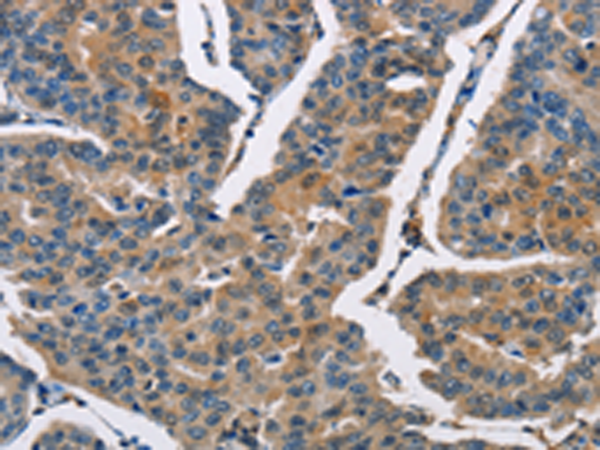

IHC positive control: |

Human breast cancer and human esophagus cancer |

IHC Recommend dilution: |

50-200 |